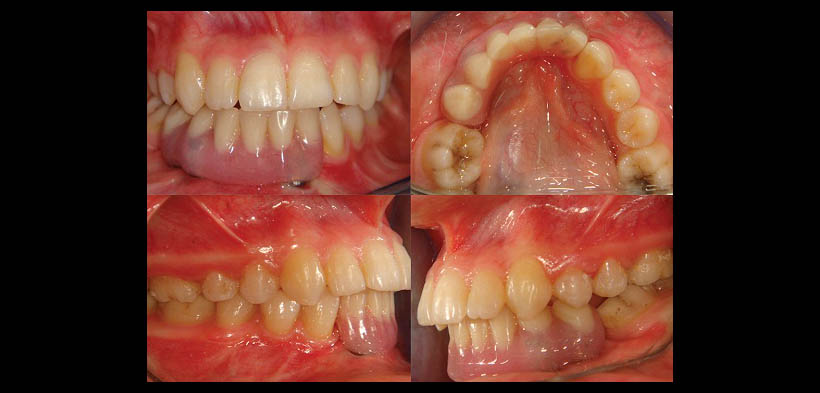

Fig. 1. Situación clínica preoperatoria de una paciente niña de 9 años con diagnóstico de GCCG.